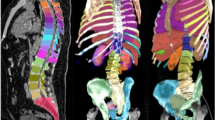

Segmentation accuracy expressed as Dice score coefficient for segmented livers (using dataset 1) and kidneys (using dataset 2) is shown in Tables 1 and 2 in comparison with other top performing methods reported in the literature. An example of a segmented left kidney, using dataset 4, for both contrast-enhanced and low-dose CT images is shown in Fig. 2. The global Dice-coefficient accuracy obtained for the segmented livers was 93.40. The kidney accuracies for the first stage (dataset 2) were 94.10 and 94.60 for the second stage (dataset 3). The values reported are for the average of fivefold cross validations of the datasets. The accuracy achieved in the consensus mode shows an increase of up to \(1.5\%\) in Dice score at the expense of independently running the network 3 times, thus triplication of the computational cost. In addition, the training without the transfer learning on ImageNet dataset provided on average \(8\%\) and \(6\%\) drops in accuracy on the test data for the liver and kidney, respectively, due to early over-fitting [35].

Segmented left kidney along axial, sagittal and coronal axis using the AI . The segmentation boundaries are highlighted with red contour on a contrast-enhanced CT on the left-hand side and on a low-dose CT on the right-hand side. The red rectangle corresponds to the bounding box used in kidney detection by the algorithm and the yellow contour is the 3 mm expanded region for activity retrieval from the SPECT images based on the CT-segmentation